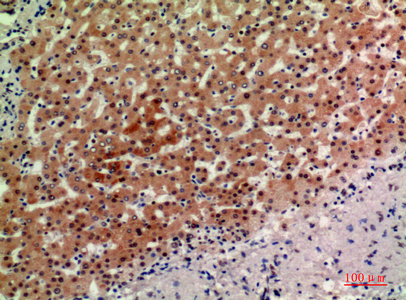

- Immunohistochemistry analysis of paraffin-embedded Human liver using ASAH3L antibody.High-pressure and temperature Sodium Citrate pH 6.0 was used for antigen retrieval.